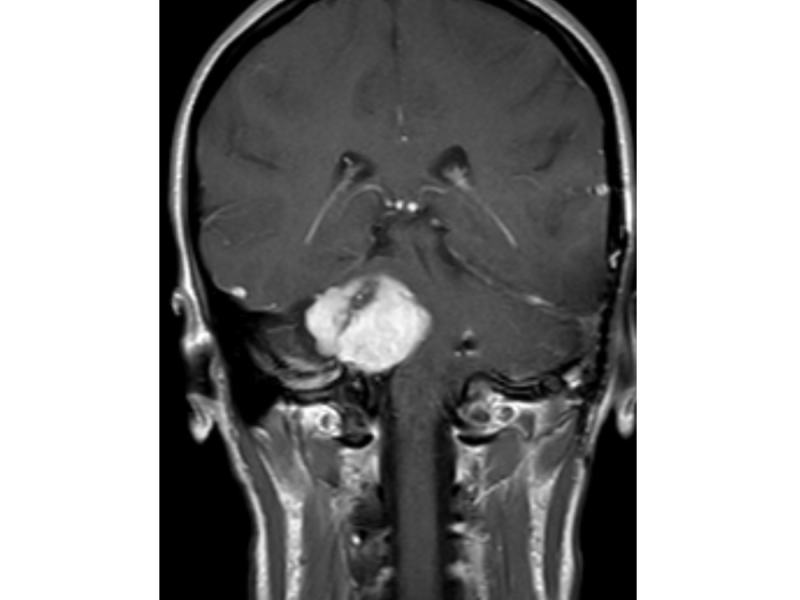

We went to the doctor the next day and after discovering that my eardrum looked healthy they decided to do an MRI. There results of the MRI found two bilateral schwannomas on my left and right auditory nerve near my brain stem.

After a lot of deliberation, my doctor decided to try to get me into a medical study that used chemotherapy to try and shrink the tumor and restore my hearing, it was the only treatment available at the time. I was in chemo for two years with quarterly MRIs scheduled. My right side tumor Stabilized but my left side kept growing. In 2017, I flew to California to have my left side of my tumour removed as it was pressing dangerously on my brain stem.

I was having vertigo problems with my coordination and balance facial nerve ticks and tinnitus. To have my surgery I went to the house clinic in California, the tumor had grown to over 6 cm meaning the surgery was 19 hours, I also received an AVI.

As a result I was fully deaf in my left ear and had partial facial paralysis from damage from the surgery, howeveer since my right side tumor had been stable I felt like I was in the clear. I had a few follow up MRIs after, before an MRI in August 2018 showed that my left side tumor had grown substantially.

Unfortunately somehow there was a lack of proper communication between me and my California doctors, meaning that I did not find out that the tumor was growing until December 2018. In January 2019 my right ear, my remaining hearing ear, had a major hearing loss drop. I have a loss of hearing of lower pitches and a 4% word association as well as tinnitus in both ears. The doctors are deliberating if I should fly to California and have a whole removal or if I should have a debulking surgery getting rid of the tumor near the brainstem and then having a few rounds of radiation to try to shrink the tumor near the hearing nervous in order to attempt to restore or retain as much hearing as I have left.

My eyesight has gotten worse as well my balance and coordination. I am still in the middle of my journey, I am learning how to cope with extreme hearing loss and learning ASL. My remaining tumour is about 4 cm now and growing into my brain stem. I have a little time to decide the next step but I am sure God will make my decision for the next step clear to me."